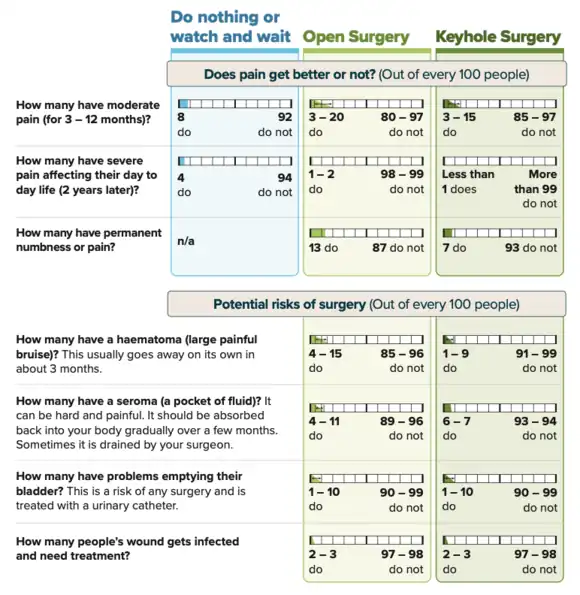

Non-surgical management

Studies have demonstrated that men whose hernias cause little to no symptoms can safely continue to delay surgery until a time that is most convenient for patients and their healthcare team. Research shows that the risk of inguinal hernia complications remains under 1% within the population.[82][20][9][21] Watchful waiting requires that patients maintain a close follow-up schedule with providers to monitor the course of their hernia for any changes in symptoms and can be safely offered for up to 2 years.[83][11]

Patients who do elect watchful waiting eventually undergo repair within five years as 25% will experience a progression of symptoms such as worsening of pain. Elective repair discussions should be revisited if patients begin to avoid aspects of their normal routine due to their hernia.[12][84][10] After 1 year it is estimated that 16% of patients who initially opted for watchful waiting will eventually undergo surgery. Furthermore, 54% and 72% will undergo repair at 5-year and 7.5-year marks respectively.[85][17]